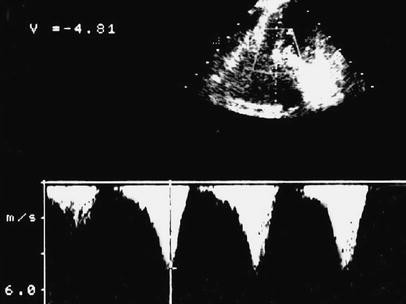

Fig. 3

figure 3

Continuous-wave Doppler shows the characteristic late-peaking high-velocity curve (Vmax=4.81 m/s) due to dynamic left ventricular outflow obstruction. GRADmax=92 mmHg

The importance of prompt and accurate diagnosis of HCM in the ICU is particularly stressed in this report. Past medical history is often unavailable or unhelpful. Patients may be asymptomatic until exacerbation or have symptoms such as exertional dyspnea and angina that can be attributed to CHF. Electrocardiographic patterns, although abnormal in most cases, are not specific for the disease [6]. PAC, which is very popular and extensively used in critical care, fails to make the diagnosis between heart diseases that may lead to pulmonary edema. Echocardiography remains the unique tool for the diagnosis of HCM. Echocardiographic findings (Figs. 2, 3) include septal hypertrophy (2.1 and 2.2 cm in our patients) with small LV cavity, systolic anterior motion of the mitral valve resulting in LVOT obstruction (92 and 108 mmHg in our patients), mitral regurgitation, and diastolic dysfunction [7]. Although HCM and dilated CHF may share common clinical and PAC findings, factors that may decompensate a patient with HCM are entirely different. A decrease in preload or afterload and/or an increase in contractility may seriously exacerbate or unmask HCM. In our two patients a decreased preload as a result of diuretics and nitrates, enhanced contractility induced by positive inotropic therapy in the recovery room, and/or release of endogenous catecholamines (e.g., postoperative pain, anxiety, and discomfort) during the weaning period in the ICUmay have caused HCM exacerbation leading to refractory pulmonary edema responsible for weaning failure.